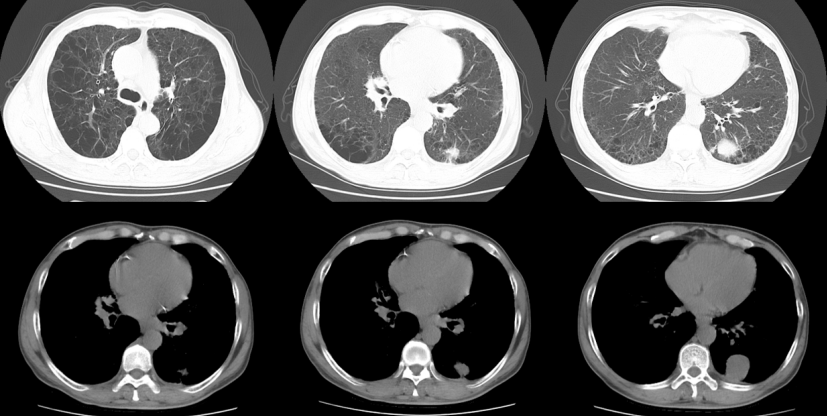

2024年3月3日BALF:鲍曼不动杆菌、白假丝酵母菌;PCT 7.614 ng/ml(↑),N-端脑利肭肽前体739.4 pg/ml。调整抗感染方案:多黏菌素E ivgtt+雾化、利奈唑胺、伏立康唑。3月3日复查胸部CT:左侧气胸,双层胸背部皮下气肿,双肺多发斑片影,左肺下叶切除术后,左侧少量胸腔积液,纵隔淋巴结肿大(图4)

4  复查胸部CT(2024-03-03)

3月10日复查胸部CT:左侧气胸,双层胸背部皮下气肿,双肺多发斑片影,双肺多发斑片影,左肺下叶切除术后,左侧少量胸腔积液,纵隔淋巴结肿大(图5)

5  复查胸部CT(2024-03-10)